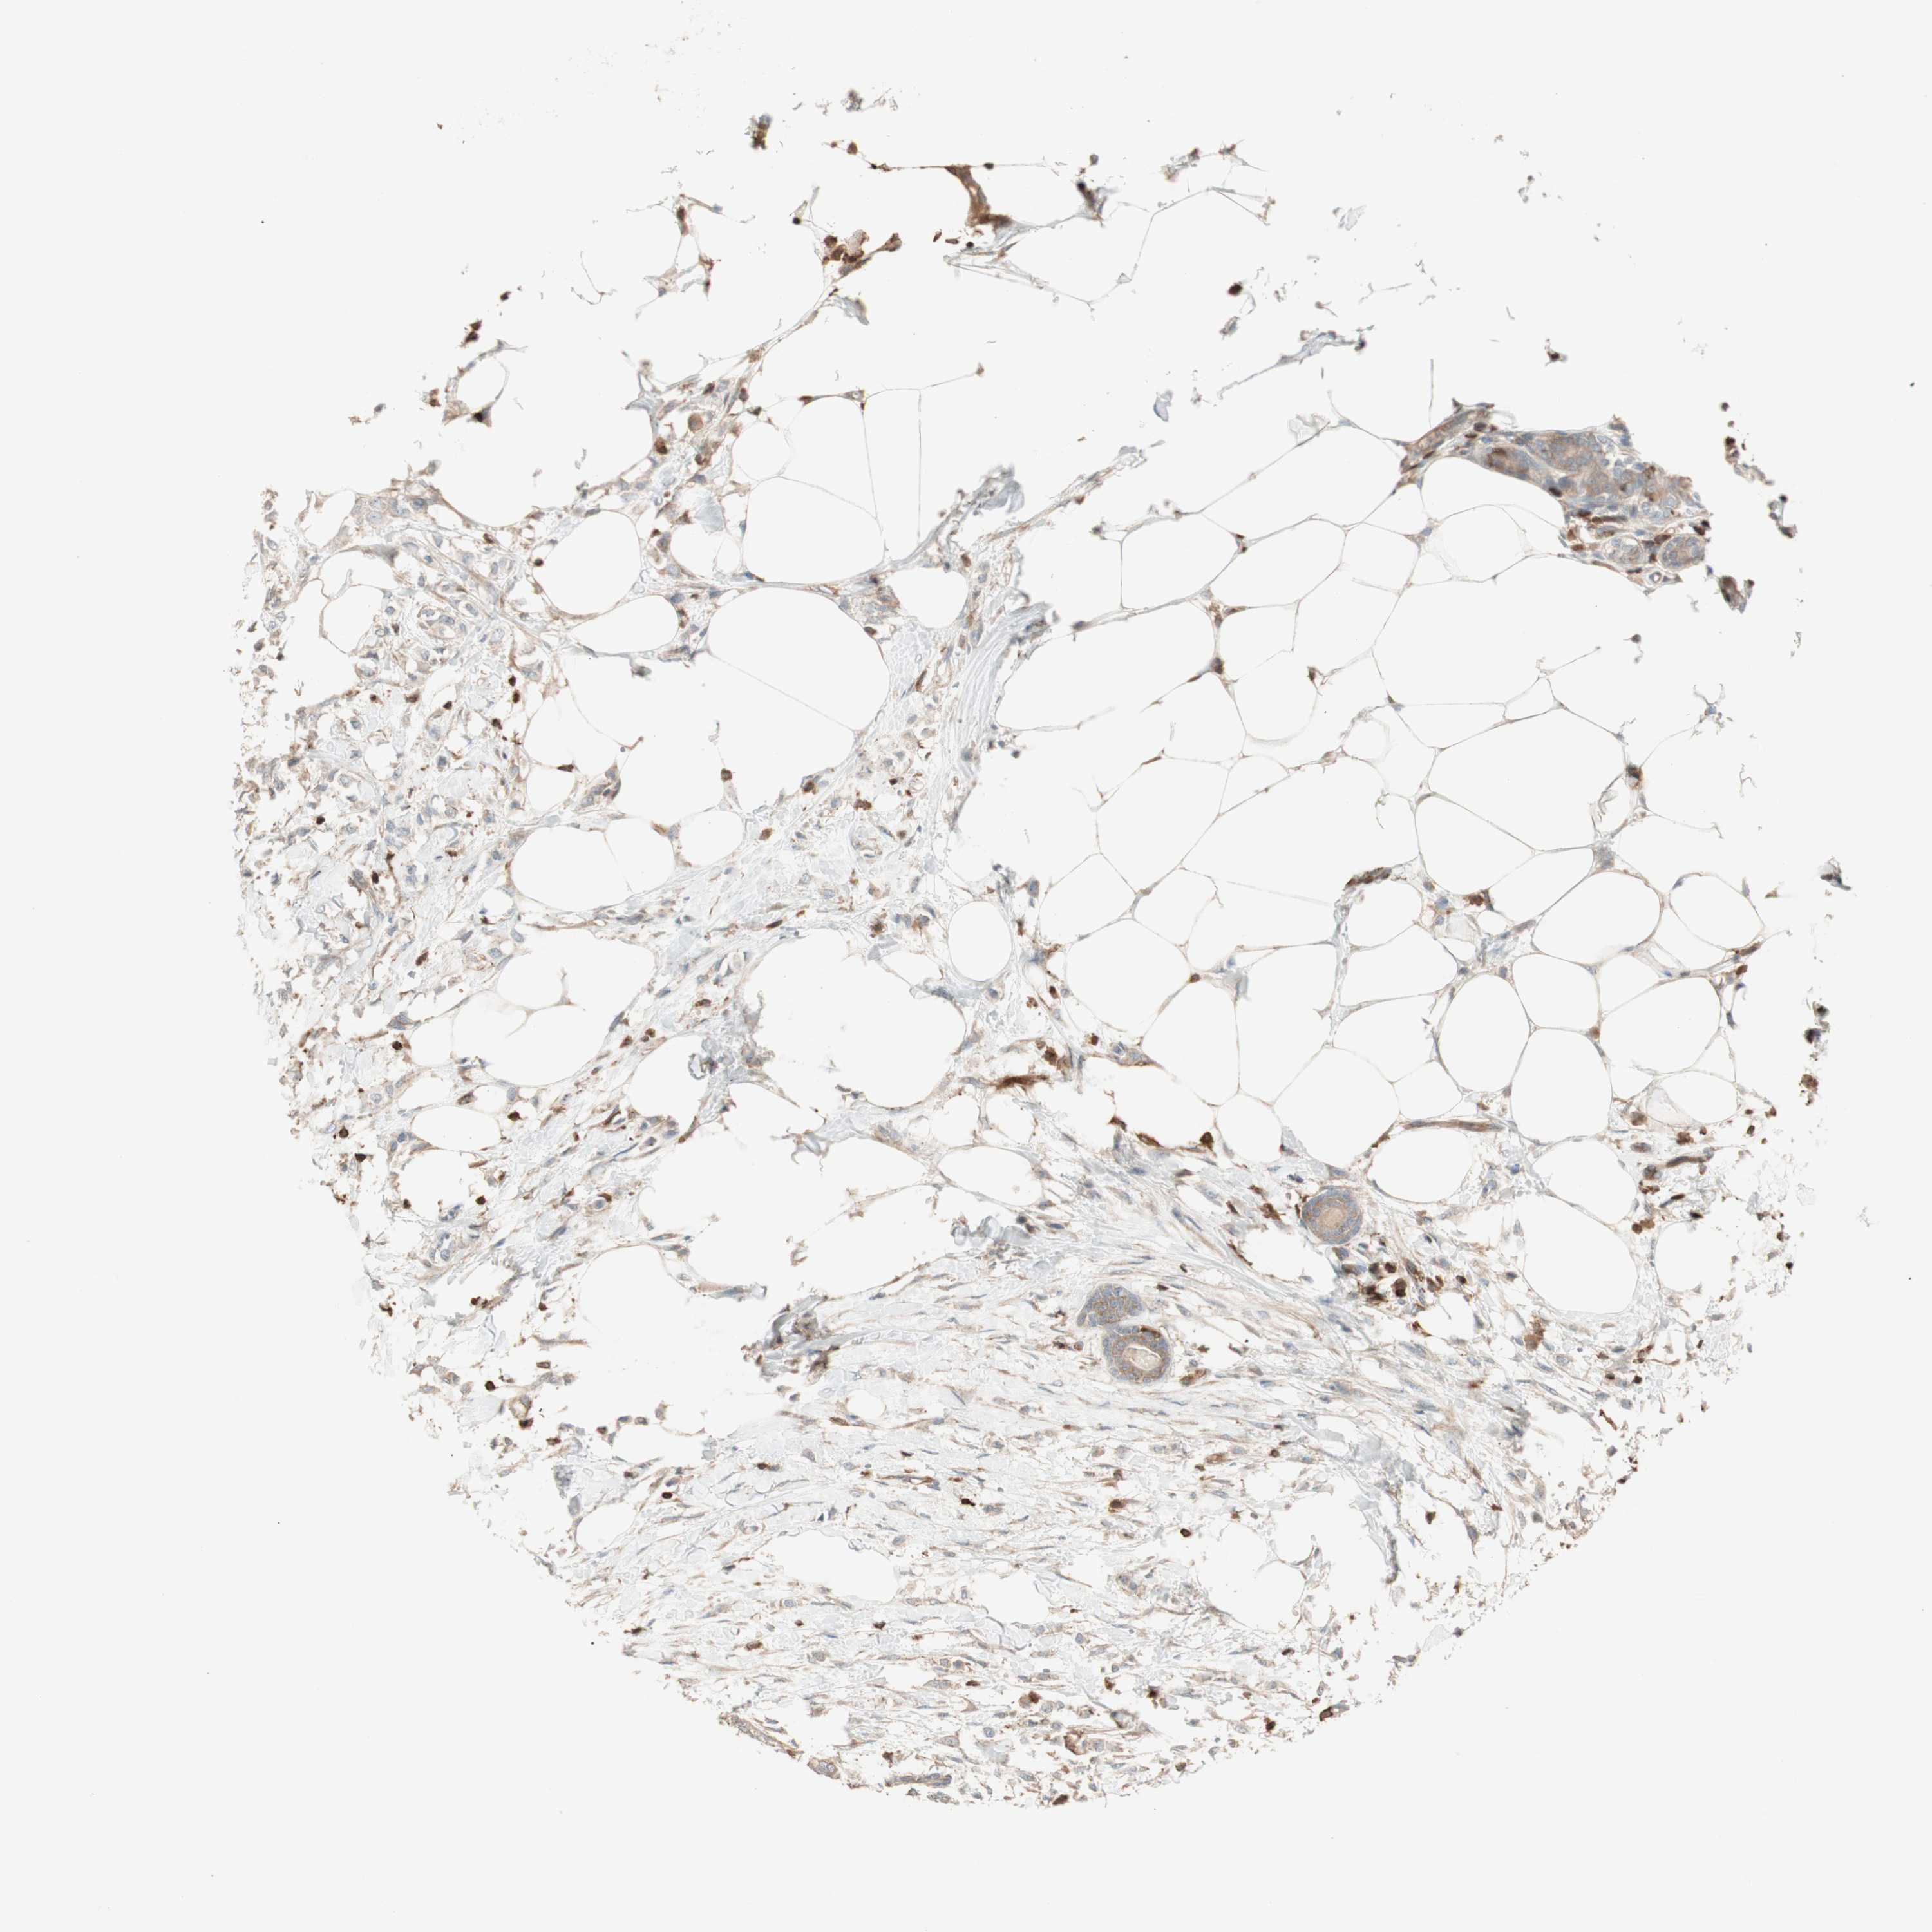

BRCA TCGA BRCA VALIDATION PROTEIN EXPRESSION